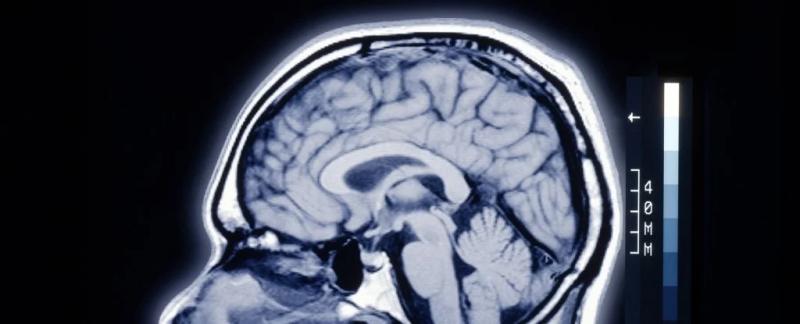

Существует странное различие между мозгом человека и мозгом других млекопитающих

Группа исследователей из Массачусетского технологического института (MIT) обнаружила, что по сравнению с другими млекопитающими человеческий мозг имеет гораздо меньшее количество нейронных каналов, которые обеспечивают поток ионов, таких как кальций, калий и натрий.

Этот поток создает электрические импульсы, которые позволяют нейронам общаться друг с другом; меньшее их количество может означать, что человеческий мозг может работать более эффективно, перенаправляя ресурсы на более сложные когнитивные функции.